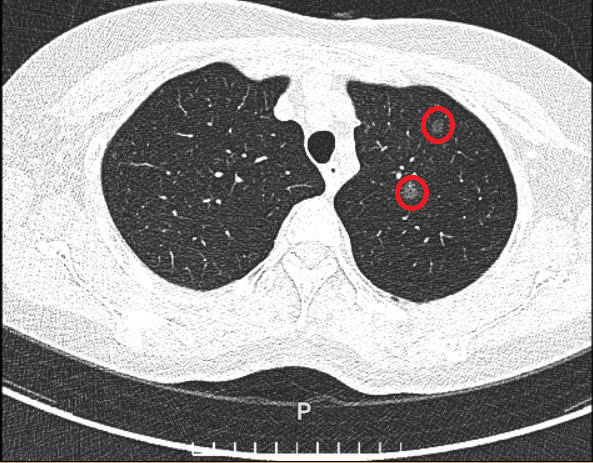

Bà Phương tiền sử hen phế quản điều trị bằng thuốc xịt, chụp CT liều thấp tại Bệnh viện Đa khoa Tâm Anh phát hiện hai nốt nhỏ ở thùy trên phổi trái. Một nốt kích thước 6,6x5,3 mm, mật độ thấp, đồng nhất, xếp loại Lung-RADS 2 (bảng phân loại nốt phổi nghi ngờ ung thư phổi). Nốt còn lại lớn, kích thước 11x5,9 mm, mật độ cao, không đồng nhất, bờ không đều, xếp hạng nguy cơ cao nhất (4X) theo LungRADS .

Với bà Phương, bác sĩ hội chẩn liên khoa chỉ định phẫu thuật nội soi cắt phân thùy phổi trái. Kết quả sinh thiết lạnh tức thời trong mổ và giải phẫu mô bệnh học hậu phẫu xác định nốt phổi nhỏ là ung thư biểu mô tuyến không chế nhầy xâm nhập tối thiểu. Nốt phổi có kích thước lớn hơn là ung thư biểu mô tuyến xâm nhập type chùm nang, độ 2. 3/3 hạch không có tế bào u di căn.